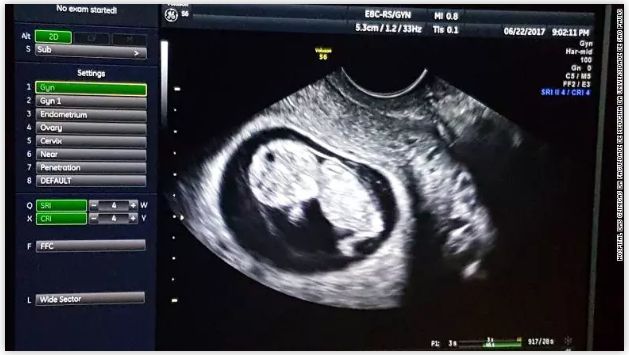

超声图显示婴儿在移植子宫内发育正常。(图片来源:CNN)

【孕期检查】孕10周时,非侵入性产检显示胎儿正常,12周和20周的超声扫描也显示没有胎儿异常。除了在孕32周时出现肾脏感染,进行了抗生素治疗,患者在整个孕期没有出现问题。